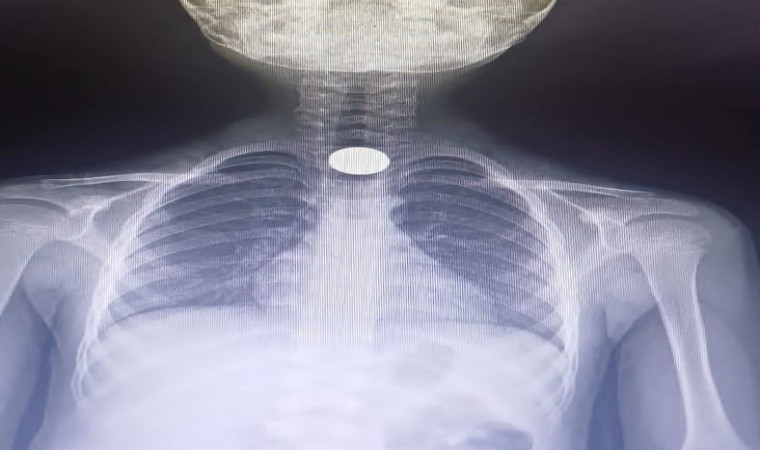

Olay, Baykoca Mahallesi Mimar Sokak’taki apartmanda meydana geldi. 7 yaşındaki Ahmet Eymen U., yerde bulduğu 50 kuruşluk madeni parayı ağzına atıp yuttu. Olayı gören ailesi çocuğu özel araçla İnegöl Devlet Hastanesine götürdü. Acilde yapılan tetkiklerde paranın yemek borusunda kaldığı tespit edildi. Çocuk, boğazındaki paranın çıkarılması için Bursa Yüksek İhtisas Eğitim ve Araştırma hastanesine sevk edildi.